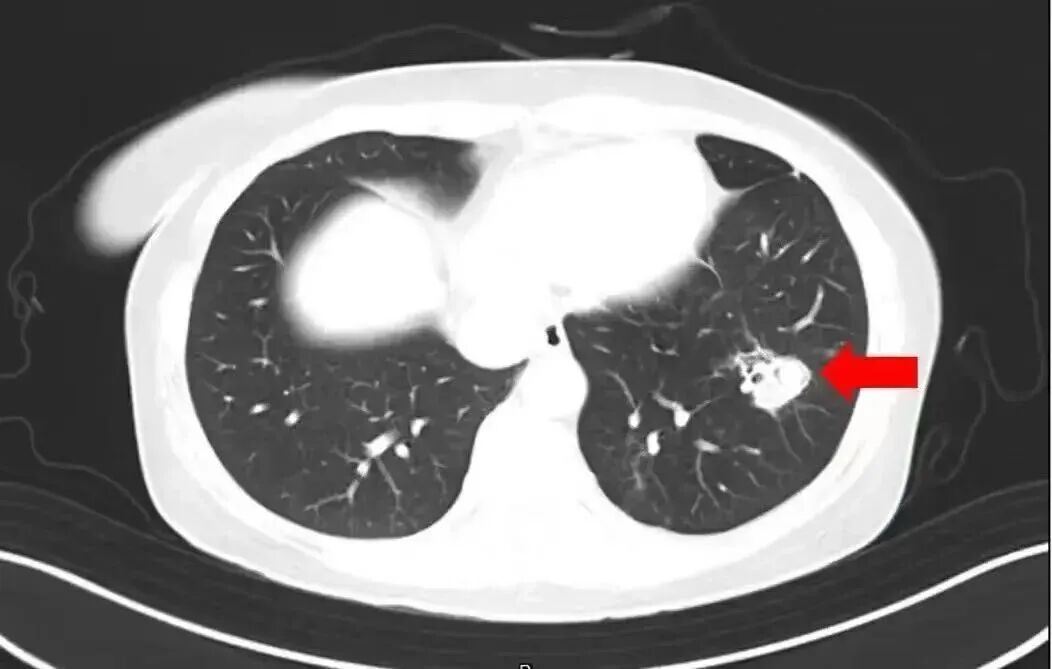

• 2025年1月,江苏扬州的张大爷为迎接春节开始大扫除,清扫过程中不慎吸入大量灰尘和霉菌孢子,导致哮喘发作。张大爷随即服用了常备的哮喘治疗药物,可症状反而逐渐加重。经检查,张大爷的肺部出现感染,确诊为肺曲霉病

医师介绍,霉菌容易随呼吸侵入鼻腔、支气管、肺部等人体呼吸系统,严重时会诱发肺部感染,还可能累及中枢神经系统,导致真菌性脑脓肿、脑膜炎等严重病症。